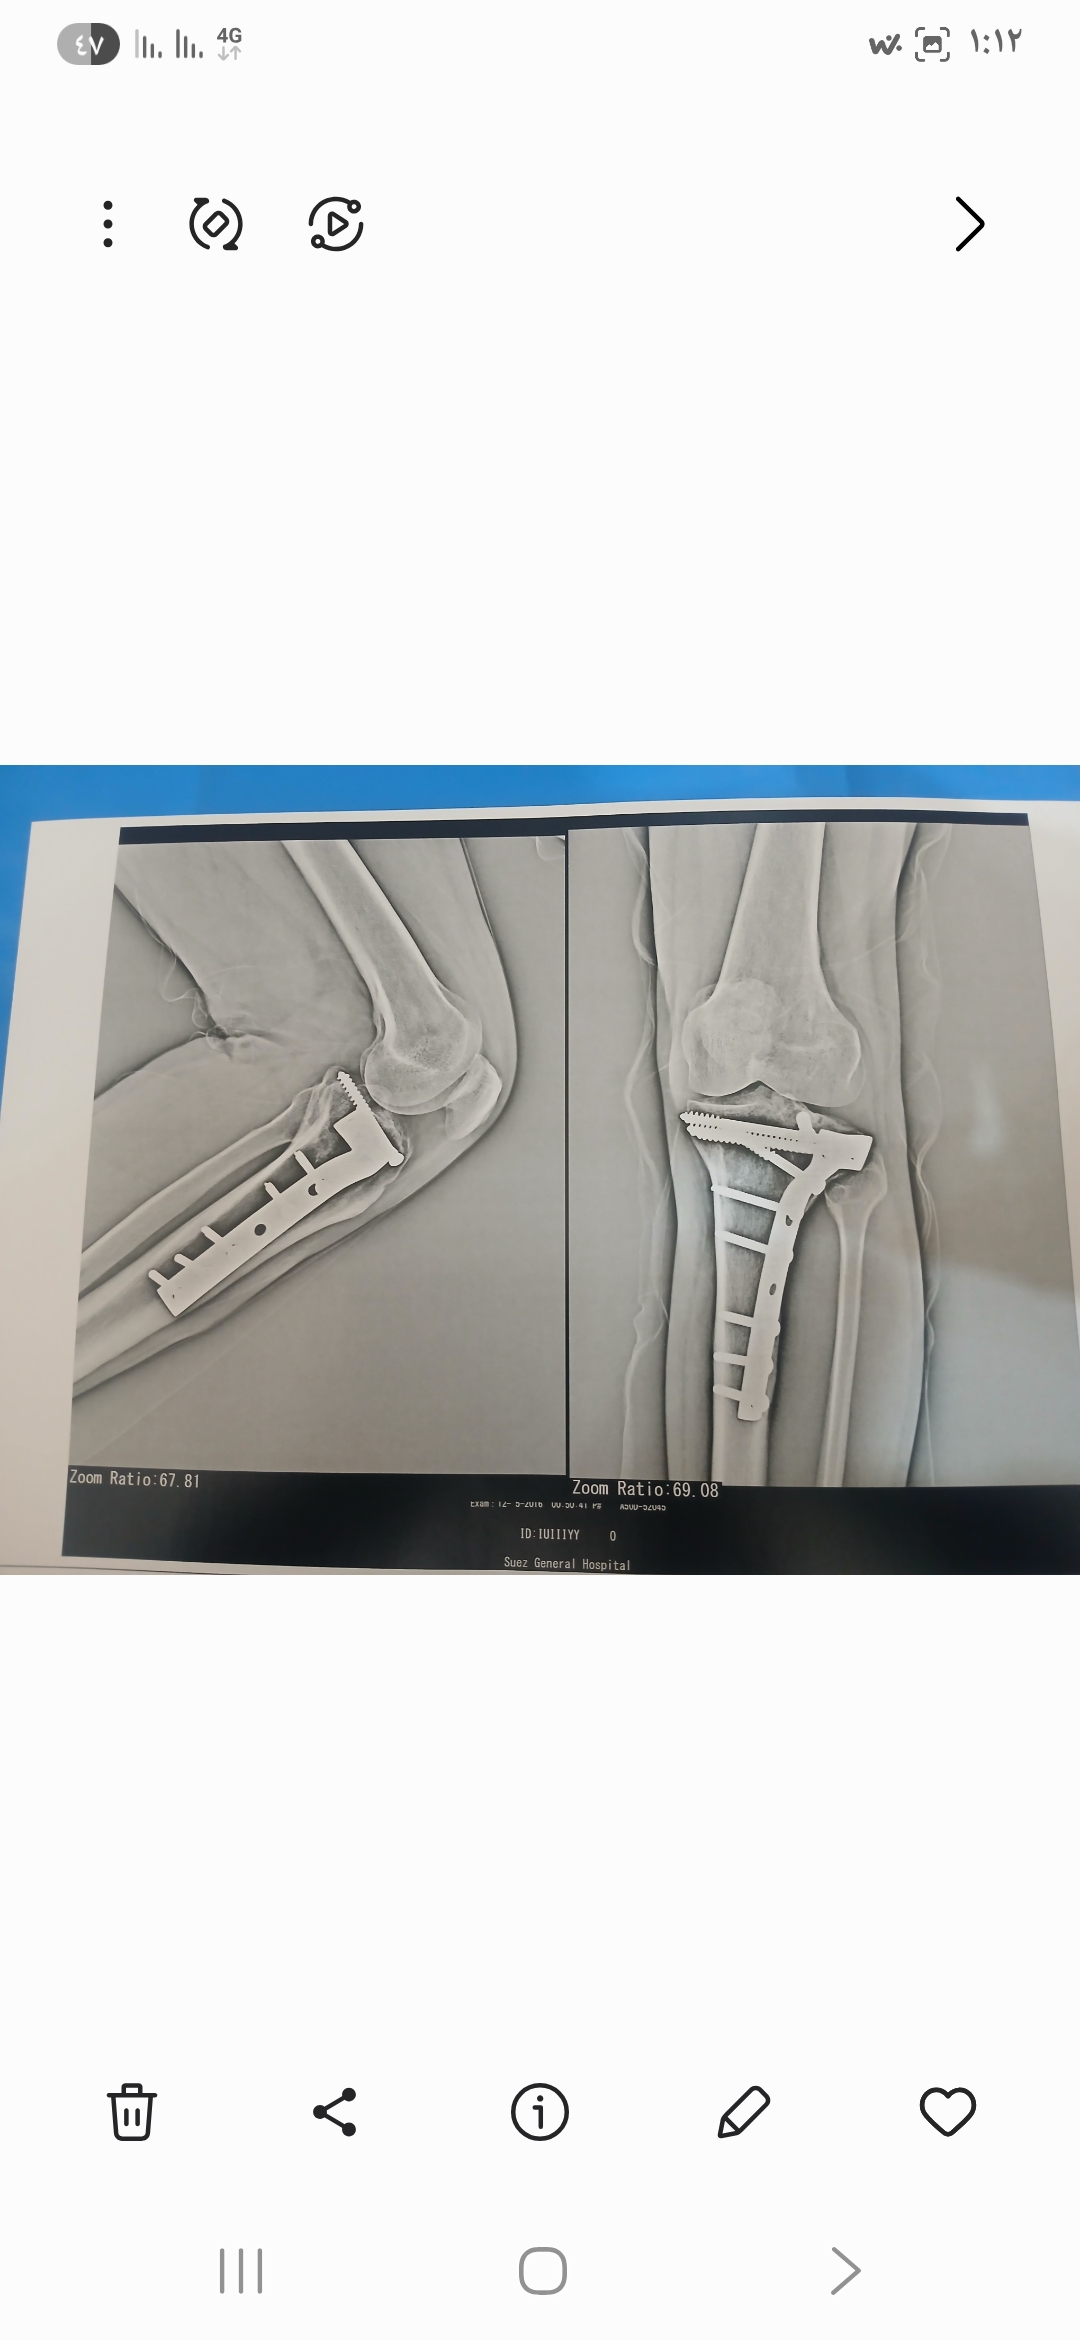

هل يوجد فرق بين صورتي الأشعة؟

كنت عاوز اعرف من دكتور عظام وأشعة في فرق بين الصورتين دي الاشعه قديمه وجديده مع بعض.

دي صورتين القديمه والجديده